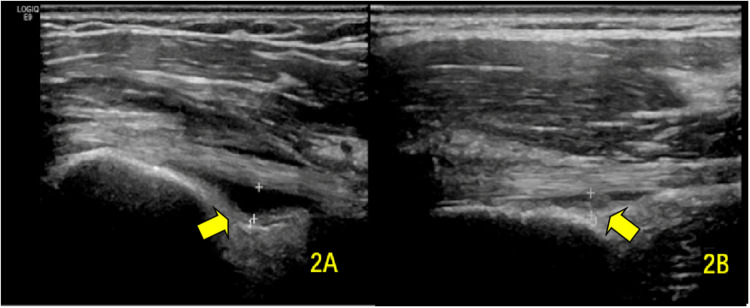

Methods: We conducted a study involving 80 stroke patients with hemiplegia and concomitant shoulder pain on the affected side, admitted to our hospital between April 2020 and March 2021. MSUS was used to evaluate shoulder structures, including the long head of the biceps brachii tendon (BICT) and its sheath, rotator cuff, subacromial-subdeltoid (SA-SD) bursa, labrum, acromioclavicular ligament, acromiocoracoid ligament, and acromion-greater tuberosity (AGT) distance. We compared pre- and post-rehabilitation measurements of supraspinatus tendon (SST) thickness, BICT sheath effusion thickness, SA-SD bursa effusion thickness, AGT distance, and visual analog scale (VAS) scores. Statistical significance was set at P < 0.05.

Results: Post-rehabilitation, the SST thickness on the hemiplegic side showed a statistically significant reduction (P = 0.023). No significant difference was observed in the mean maximum rupture diameter (P = 0.796). Both BICT sheath effusion (P < 0.001) and SA-SD bursa effusion (P < 0.001) exhibited significant decreases. The AGT distance on the hemiplegic side also demonstrated a statistically significant change (P < 0.001). Additionally, the VAS score significantly improved post-rehabilitation (P < 0.001).

Abstract Image